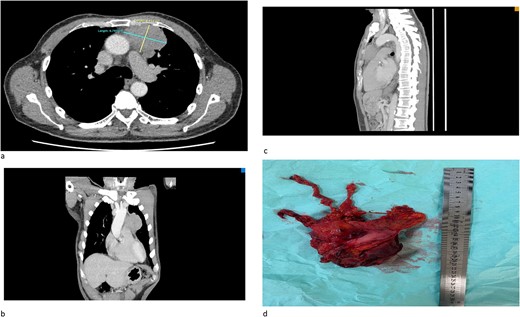

(a) An axial cut of a contrast-enhanced computed tomography (CECT) scan thorax showing an ill-defined anterior mediastinal mass measuring 4.8 cm × 6.7 cm. (b) A coronal view of a CT scan showing an ill-defined anterior mediastinal mass infiltrating the left upper and middle lobe lung. (c) A sagittal view of a CT scan showing an ill-defined anterior mediastinal mass. (d) A successful total thymectomy with R0 resection (microscopically margin-free resection) through a primary median sternotomy.

The patient successfully underwent total thymectomy with pericardium, lower part of upper lobe, and upper part of the lower lobe of the left lung en bloc resection (Fig. 1d). The patient was discharged well. The histopathology (HPE) specimens were reported as poorly differentiated cancer with lung invasion (T3N1MX). He was then referred to the oncology team, and successfully completed four cycles of adjuvant chemotherapy using the ‘paclitaxel carboplatin regime’. His follow-up investigations showed complete resolution of hyponatremia and his symptoms revolved after completion of chemotherapy.